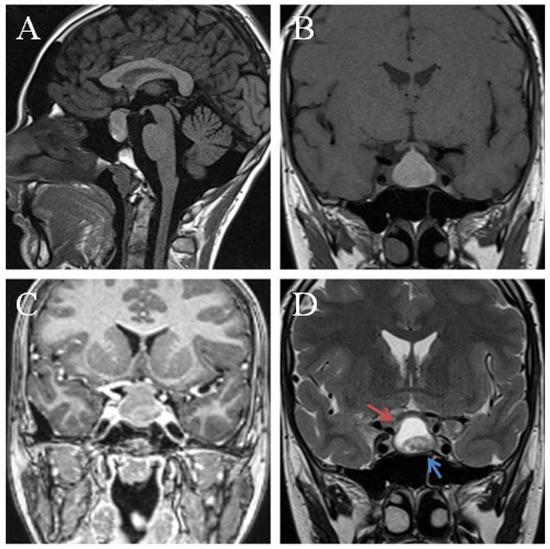

4.2. Sellar Xanthogranulomas MRI Pattern of Morphology

4.5. Pituitary Gland Appearance on MRI

4.6. Additional Signs